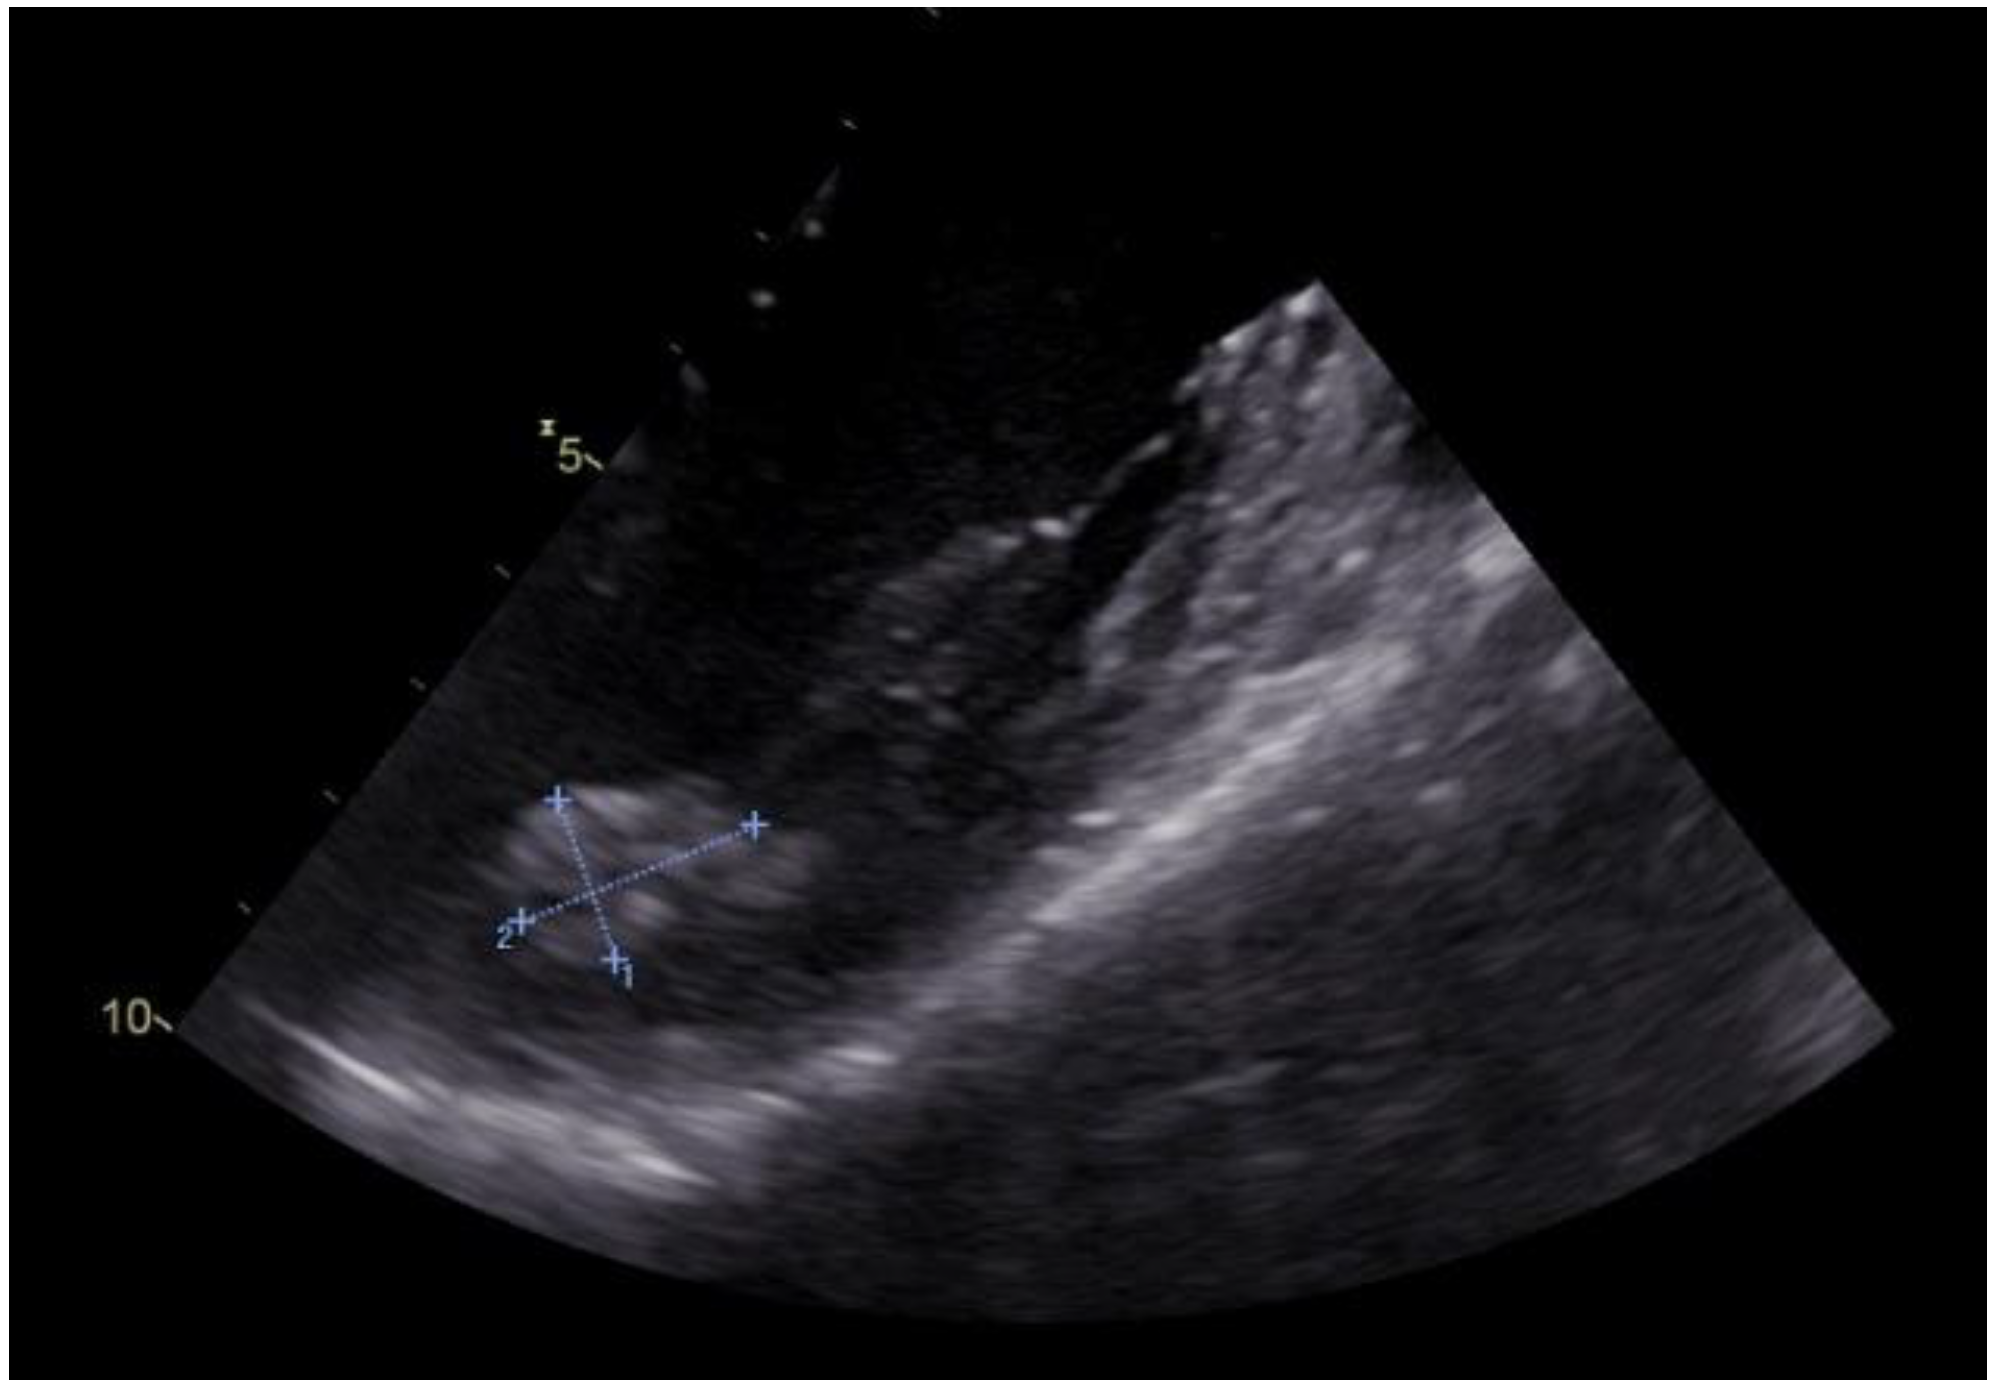

2. Case Report